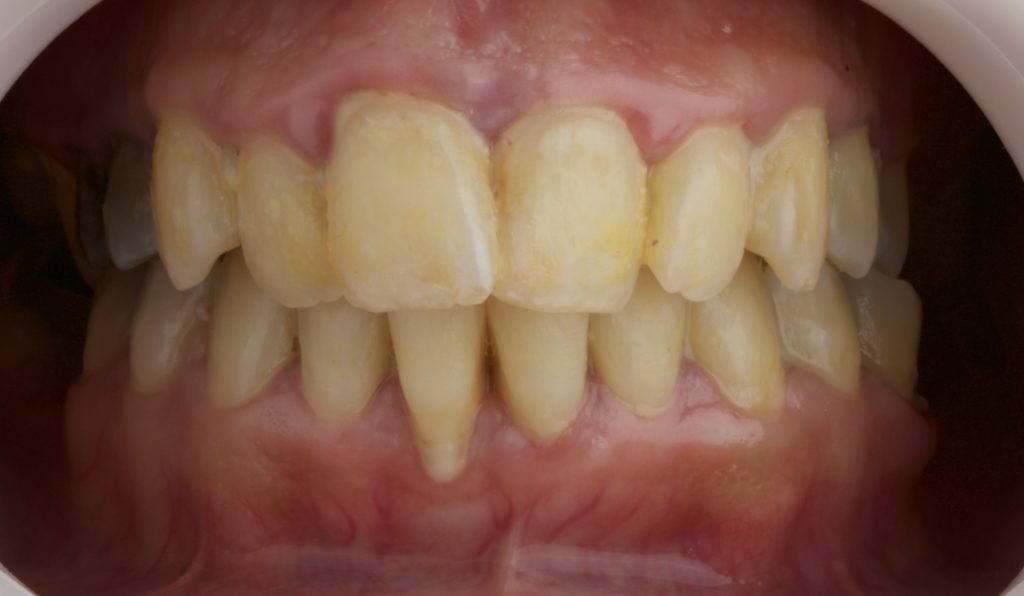

- Shade change achieved from 4M3 to 2R1.5.

- Noticeable esthetic enhancement with a shade improvement of more than two steps on the VITA scale.

The shade transition from 4M3 to 2R1.5 highlights the efficacy of the combined protocol used.

The integration of scaling, air polishing, and laser-assisted bleaching using FGM Blue Kit successfully improved both oral health and smile esthetics in this patient with stage III periodontitis and extrinsic discoloration